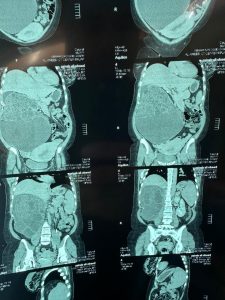

و تم إجراء عمليه نوعيه كبرى لإستئصال الكليه اليمنى الجذري لمريضة تبلغ من العمر 30 عاماً يوم أمس الأحد ، بعد إكتشاف ورم ضخم يزن حوالي 10 كغم .

و بين الدليمي : بعد إجراء الفحوصات الشعاعيه و المختبريه ، تبين وجود ورم كبير في الكلية اليمنى ، يشغل معظم التجويف البطني للمريضه .